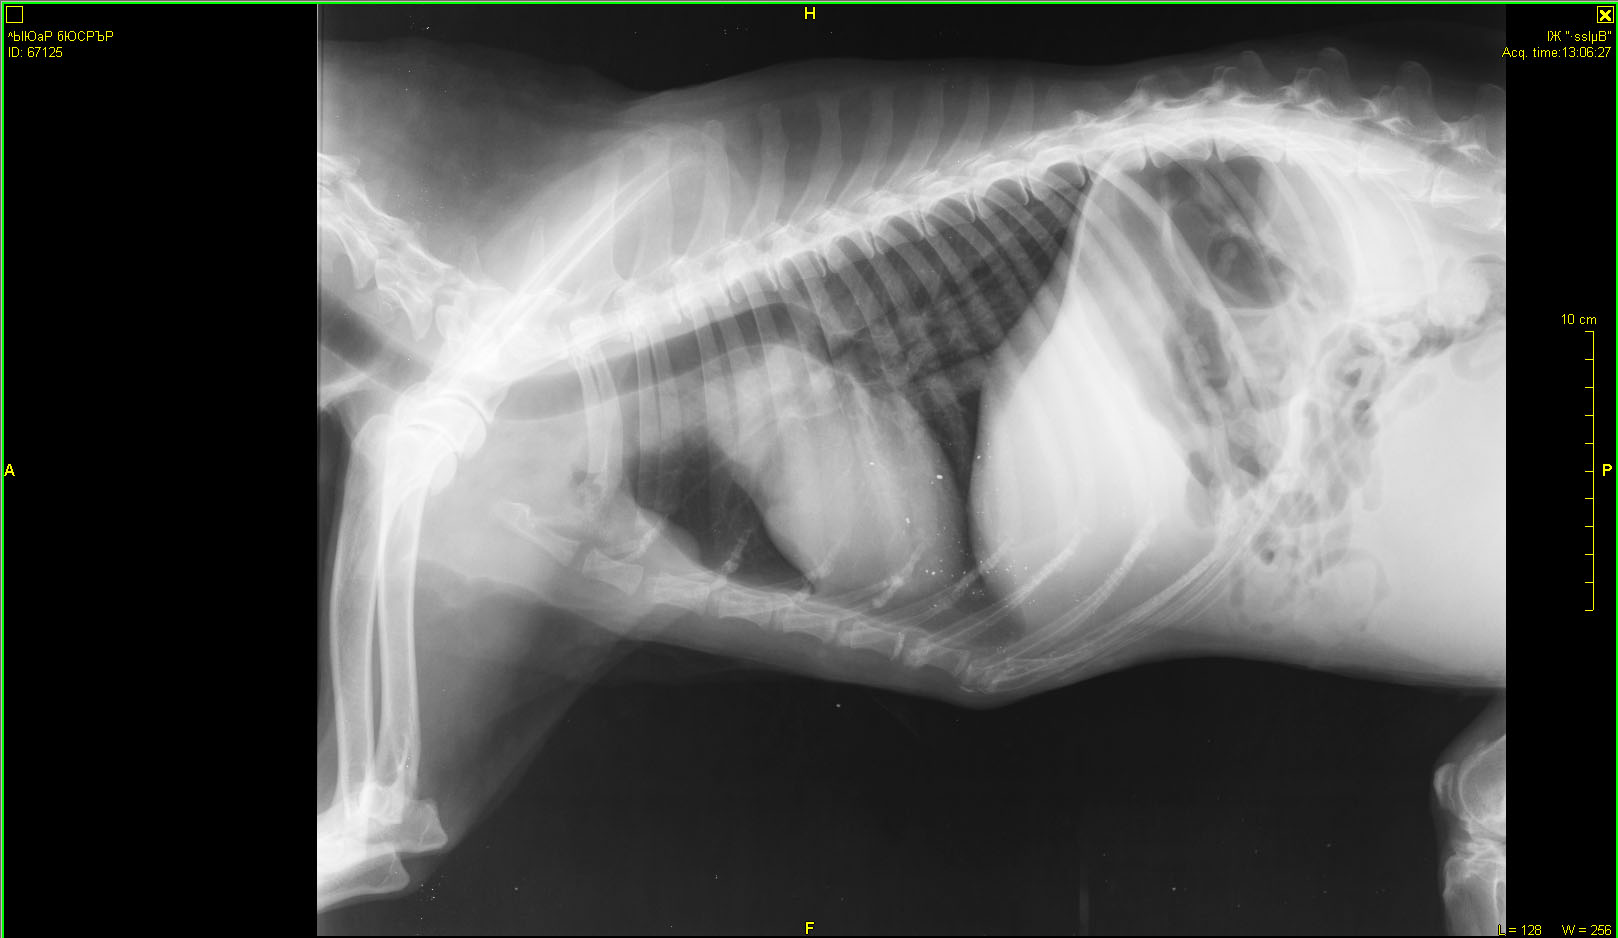

Рентген в Зоовете. Может, кто разбирается, что скажет?

"Вкратце. Новообразования в мочевом пузыре и в позвоночнике, раздробился позвонок, про который думали, что перелом. Был уж там перелом раньше или нет, сейчас уже не важно. Проблемы с мочевым - сам не мочится, только когда переполняется, но переполняться нельзя. Спасаемся катетером. Ну и плюс, конечно, повреждения спинного мозга, сильная обезвоженость, интоксикация, я всего не запомнила, Галина Юрьевна больше во всём разбирается, я выложу сейчас результаты анализов. Капельницы по 4 часа 2 раза в день, сейчас капается. Врач ставит онкологию, скорее всего злокачественную, это не достоверно, но скорее всего. Операцию смысла делать нет, потому что в её состоянии она не выдержит. Предложил или усыпить сразу, или капать и смотреть дальше по состоянию. Он не уверен, что она проживёт и более 5 дней. Хотя вот вчера и сегодня утром чуть курочки поела, сейчас ещё попробую дать. Но слабая конечно. Постоянно пьёт. Сейчас всё сосканирую и выложу.

Хотим показать результаты обследований Гаранину. Может быть, если состояние улучшиться, рискнём на операцию. Или во Владимире Ильину. "